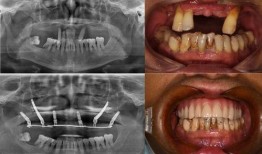

最近佛山那边的种牙事件可是闹得沸沸扬扬的,咱们得好好来聊聊这个话题。你有没有看过那个爆料视频?简直让人瞠目结舌啊!事件回顾:佛山...